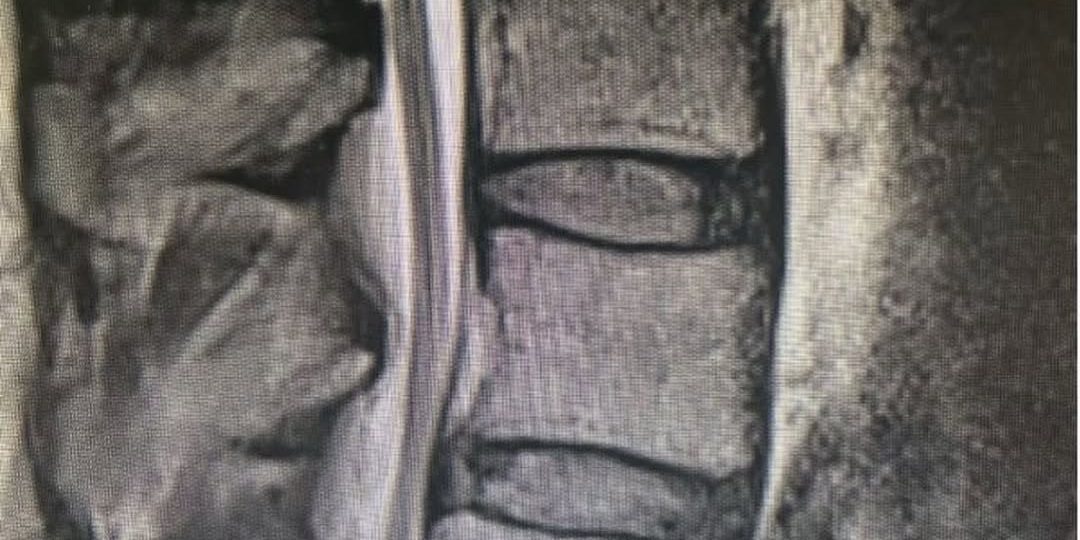

Image 1: This patient had spinal stenosis at L4-5 on MRI that looks straightforward as the first image shows.

Image 2: The X-rays revealed that he had severe spinal stenosis as the L4 and L5 as well as spondylolisthesis, which caused instability.